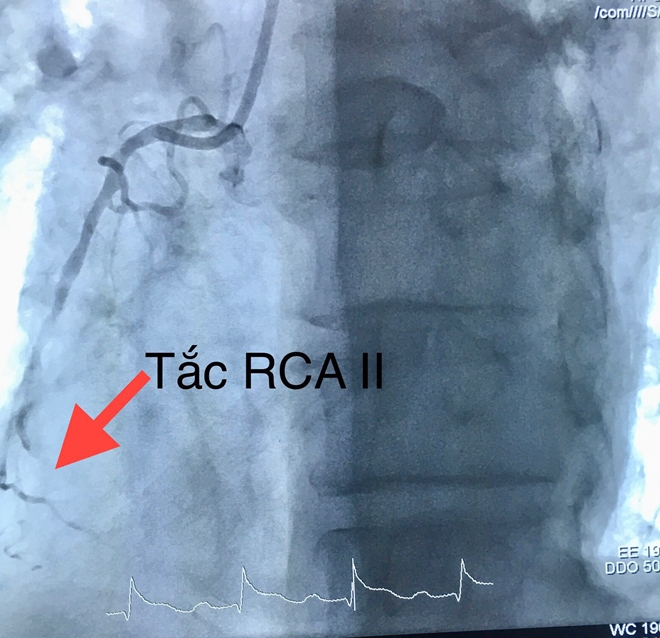

Tại đây, bệnh nhân được chẩn đoán nhồi máu cơ tim cấp thành dưới giờ thứ 4 biến chứng ngưng tim do rối loạn nhịp (rung thất) đã cấp cứu thành công. Bệnh nhân được chỉ định chụp, can thiệp mạch vành cấp cứu và chuyển thẳng đến phòng can thiệp.

Các bác sĩ tiến hành dùng bóng nong động mạch vành phải và đặt một stent phủ thuốc. Thời gian tái thông mạch vành 20 phút.

| Hình ảnh tắc động mạch vành. |